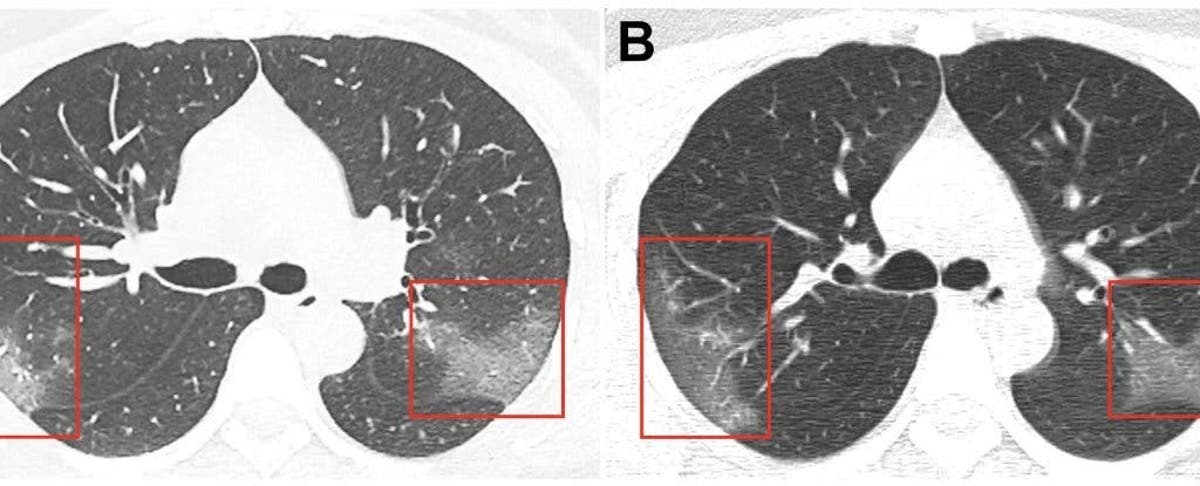

Ct Scans Show Lung Injury In Asymptomatic Carriers Of Covid 19 Axis Imaging News

Studies Profile Lung Changes In Asymptomatic Covid 19 Viral Loads In Patient Samples Cidrap

Ct Reveals Lung Injury In Asymptomatic Covid 19 Carriers General Imaging Medimaging Net

Asymptomatic Novel Coronavirus Pneumonia Patient Outside Wuhan The Value Of Ct Images In The Course Of The Disease Clinical Imaging